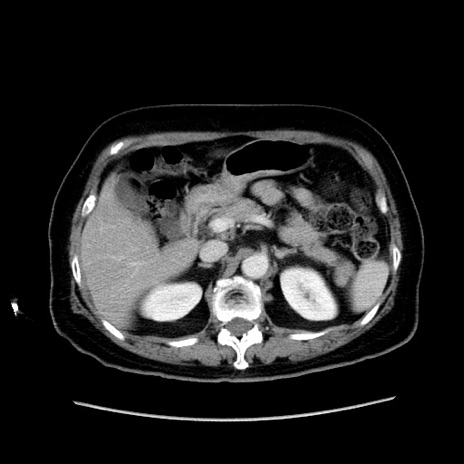

症例19(横断像)

【症例】80歳代女性

【主訴】下腹部痛

【現病歴】約8時間前より下腹部痛の出現あり、救急外来受診。

【既往歴】両側付属器切除

【身体所見】意識清明、下腹部正中に手術痕あり、その部位に一致して圧痛と反跳痛あり。腸蠕動音は亢進。

【データ】WBC 9300、CRP 0.15